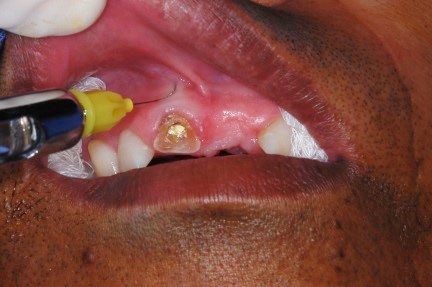

- Figura 1 – Radiografia panorâmica.